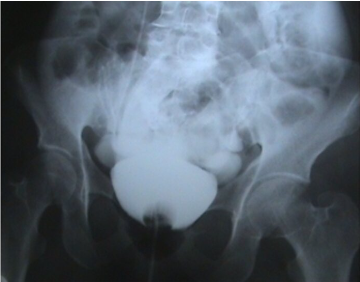

_____ is the next best step to manage a case of intraperitoneal bladder rupture